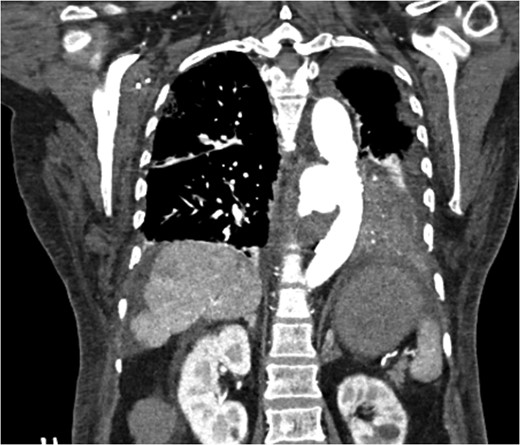

CT scan chest/abdomen/pelvis coronal view. Thoracic pseudoaneurysm distal to the left subclavian artery take off and proximal to the origin of the celiac artery.

Pseudoaneruysm size, anatomical location (distal to aortic arch and above the celiac artery) made it feasible for TEVAR. In the operating room a right groin dissection was performed, stent graft was deployed through right femoral artery and postoperative fluoroscopy imaging showed exclusion of the sac with excellent contained flow within aortic lumen.